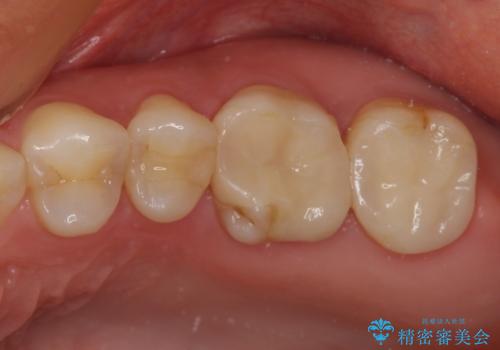

- 奥歯がズキズキと痛み、食事で噛むことができないとのことで来院された患者様です。

以前治療を受けたとき、むし歯が大きかったため、神経組織が炎症を起こす可能性があると指摘をされていたとのことでした。

レントゲン写真から、神経組織近くにまで大きな修復物が認められました。

叩いたり、冷熱や電気刺激にによるテストを行ったりとしましたが、炎症の状態は芳しくなく、根管治療を行う前提で処置を行うこととしました。